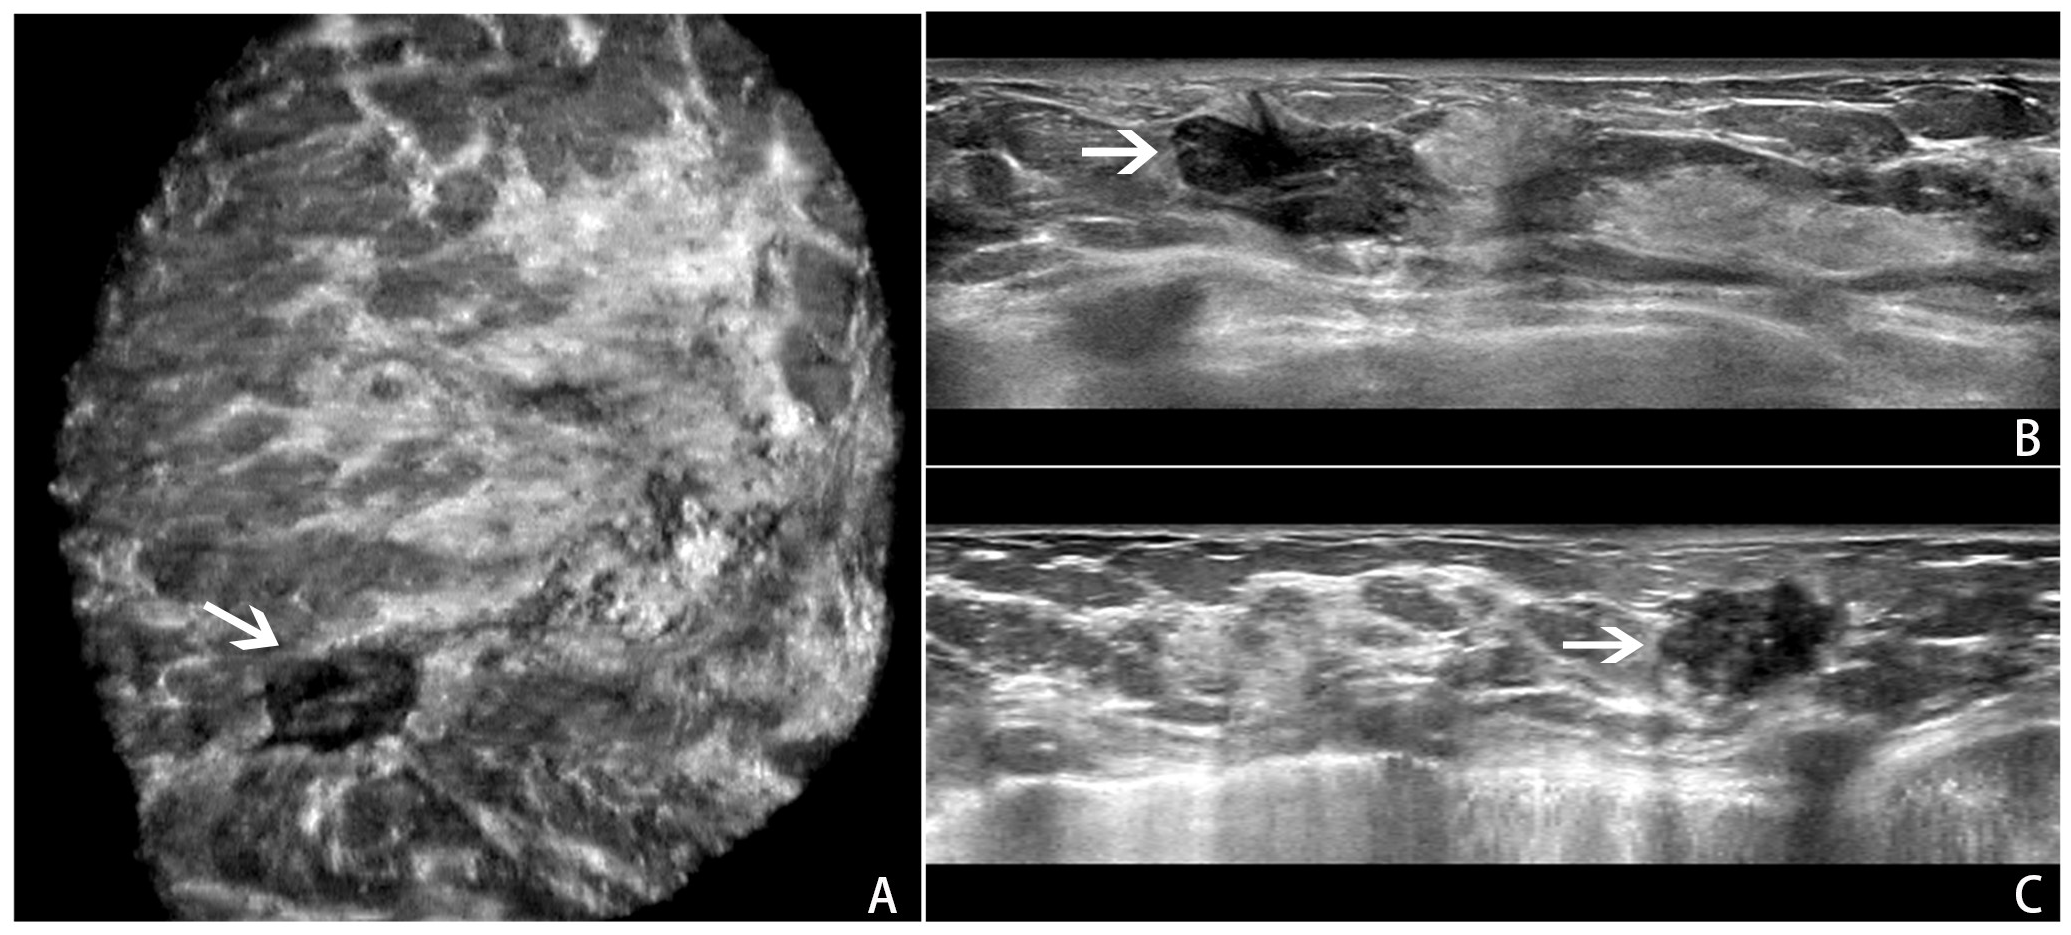

All ABVS examinations were performed by the Acuson S2000 ABVS (Siemens, Germany) ultrasound systems with the 14L5BV probe (5–14 MHz) by two technicians (with 6 months of ABVS training experience). For more details on the ABVS examination, see Kim et al (22). After the examination, axial ABVS images were sent to a dedicated workstation, and the sagittal and coronal images were reconstructed automatically. Finally, the axial, sagittal, and coronal ABVS images showing the largest lesions were selected for further segmentation and classification. An example is shown in Figure 1.

Figure 1

An example of a BI-RADS 4 lesion on ABVS images.ABVS images of the largest sections of a lesion in the coronal (A), axial (B), and sagittal (C) planes.